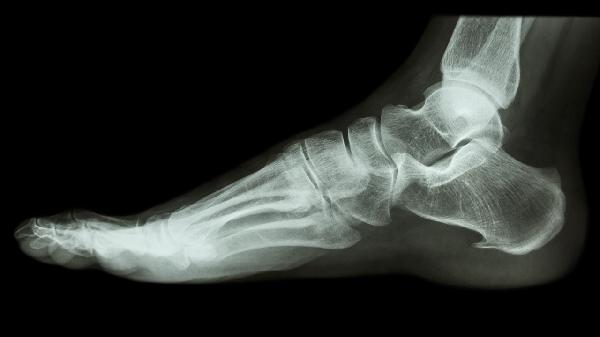

趾骨的常见疾病主要有趾骨骨折、趾间关节炎、拇外翻、痛风性关节炎和骨髓炎,按病情从轻到重排列。

趾骨骨折多由外伤导致,如重物砸伤或运动损伤。表现为局部肿胀、疼痛和活动受限。轻微骨折可通过石膏固定治疗,严重移位需手术复位。可遵医嘱使用接骨七厘片、伤科接骨片等中成药辅助愈合,或使用布洛芬缓释胶囊缓解疼痛。

趾间关节炎常与劳损、退行性变有关,早期表现为晨僵和间歇性隐痛。建议减少负重活动,配合热敷缓解症状。急性发作期可遵医嘱使用双氯芬酸钠缓释片、塞来昔布胶囊等抗炎药物,或局部注射玻璃酸钠改善关节功能。

拇外翻多与遗传和穿鞋不当相关,特征为第一跖趾关节畸形突出。轻度可通过矫形器和足弓垫矫正,严重畸形需行截骨矫形术。日常应选择宽头鞋,避免穿高跟鞋。疼痛时可使用洛索洛芬钠贴剂缓解症状。

痛风性关节炎由尿酸结晶沉积引发,常见于第一跖趾关节,表现为突发剧痛和皮肤发亮。急性期需限制嘌呤饮食,遵医嘱服用秋水仙碱片、非布司他片等药物。慢性期可配合苯溴马隆片控制血尿酸水平。

骨髓炎多为细菌感染所致,伴随持续疼痛、发热和局部红肿。需静脉使用注射用头孢呋辛钠等抗生素,严重者需手术清创。糖尿病足患者更易发生,需严格控制血糖。恢复期可配合康复新液促进创面愈合。